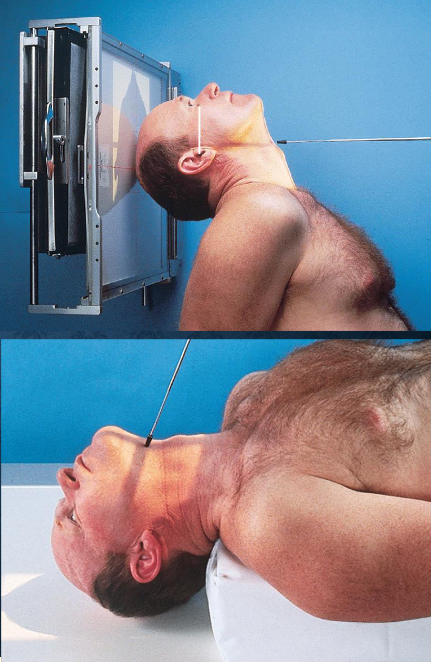

SMV (Schuller) skull

patient position:

upright (seated) or supine (torso elevated)

part position:

MSP centered to midline

MSP perpendicular to IR

IOML parallel with IR

patient hyperextends neck and rests head on vertex

respiration suspended

CR:

perpendicular through sella turcica and IOML

enters MSP of throat between angles of mandible (gonion)

passes through a point ¾ inch anterior to the level of the EAM

collimation:

½ inch beyond the shadow of the tip of the nose and 1 inch beyond the lateral borders

SMV (Schuller) skull image criteria

no rotation or tilt:

equal distance from lateral border of skull to mandibular condyles

symmetric petrous pyramids

penetration sufficient to demonstrate structures of cranial base

superimposition of mental protuberance over anterior frontal bone, indicating full neck extension

mandibular condyles anterior to petrous pyramids